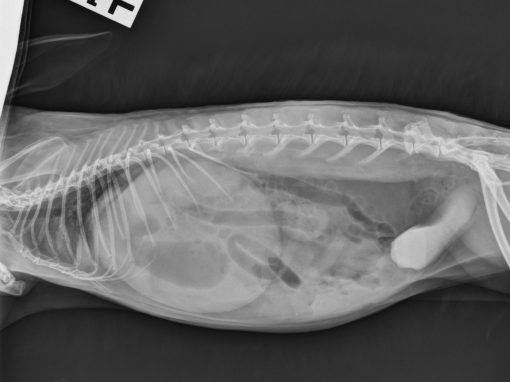

Photo reference: